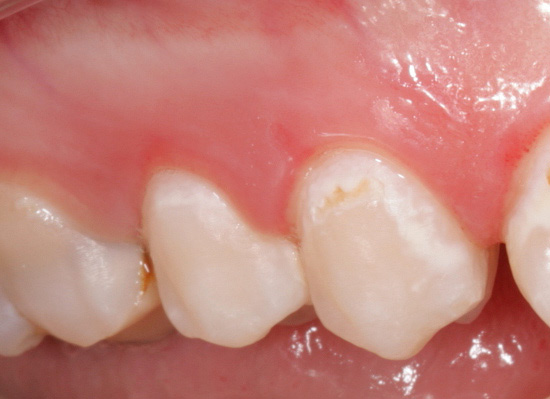

L'ispezione visiva dei denti è il modo principale per identificare una situazione cariogena nella cavità orale. La carie è caratterizzata dal fatto che in quasi tutte le fasi del suo corso, cambia il colore dello smalto dei denti. Anche nella fase spot, quando la dentina non è ancora interessata, lo smalto cessa di essere liscio e lucido e il dentista attento nota facilmente un tale cambiamento.

In fasi successive, determinare la carie con un semplice esame è ancora più semplice: porta alla comparsa di punti neri e marrone scuro sui denti o quando la dentina è danneggiata, sotto lo smalto sono visibili cavità scure.

In generale, puoi diagnosticare autonomamente la carie in te stesso notando eventuali anomalie nel colore bianco puro naturale dello smalto dei denti. Particolare attenzione deve essere ispezionata nelle aree vicino a otturazioni, patatine, sopra le gengive. È anche necessario prestare attenzione alla sensibilità dei denti. A volte lo smalto è scheggiato sui denti anteriori, il che provoca dolore nella respirazione. I luoghi di tali chip sono il "gateway" per la sconfitta delle aree esposte da batteri cariogeni.